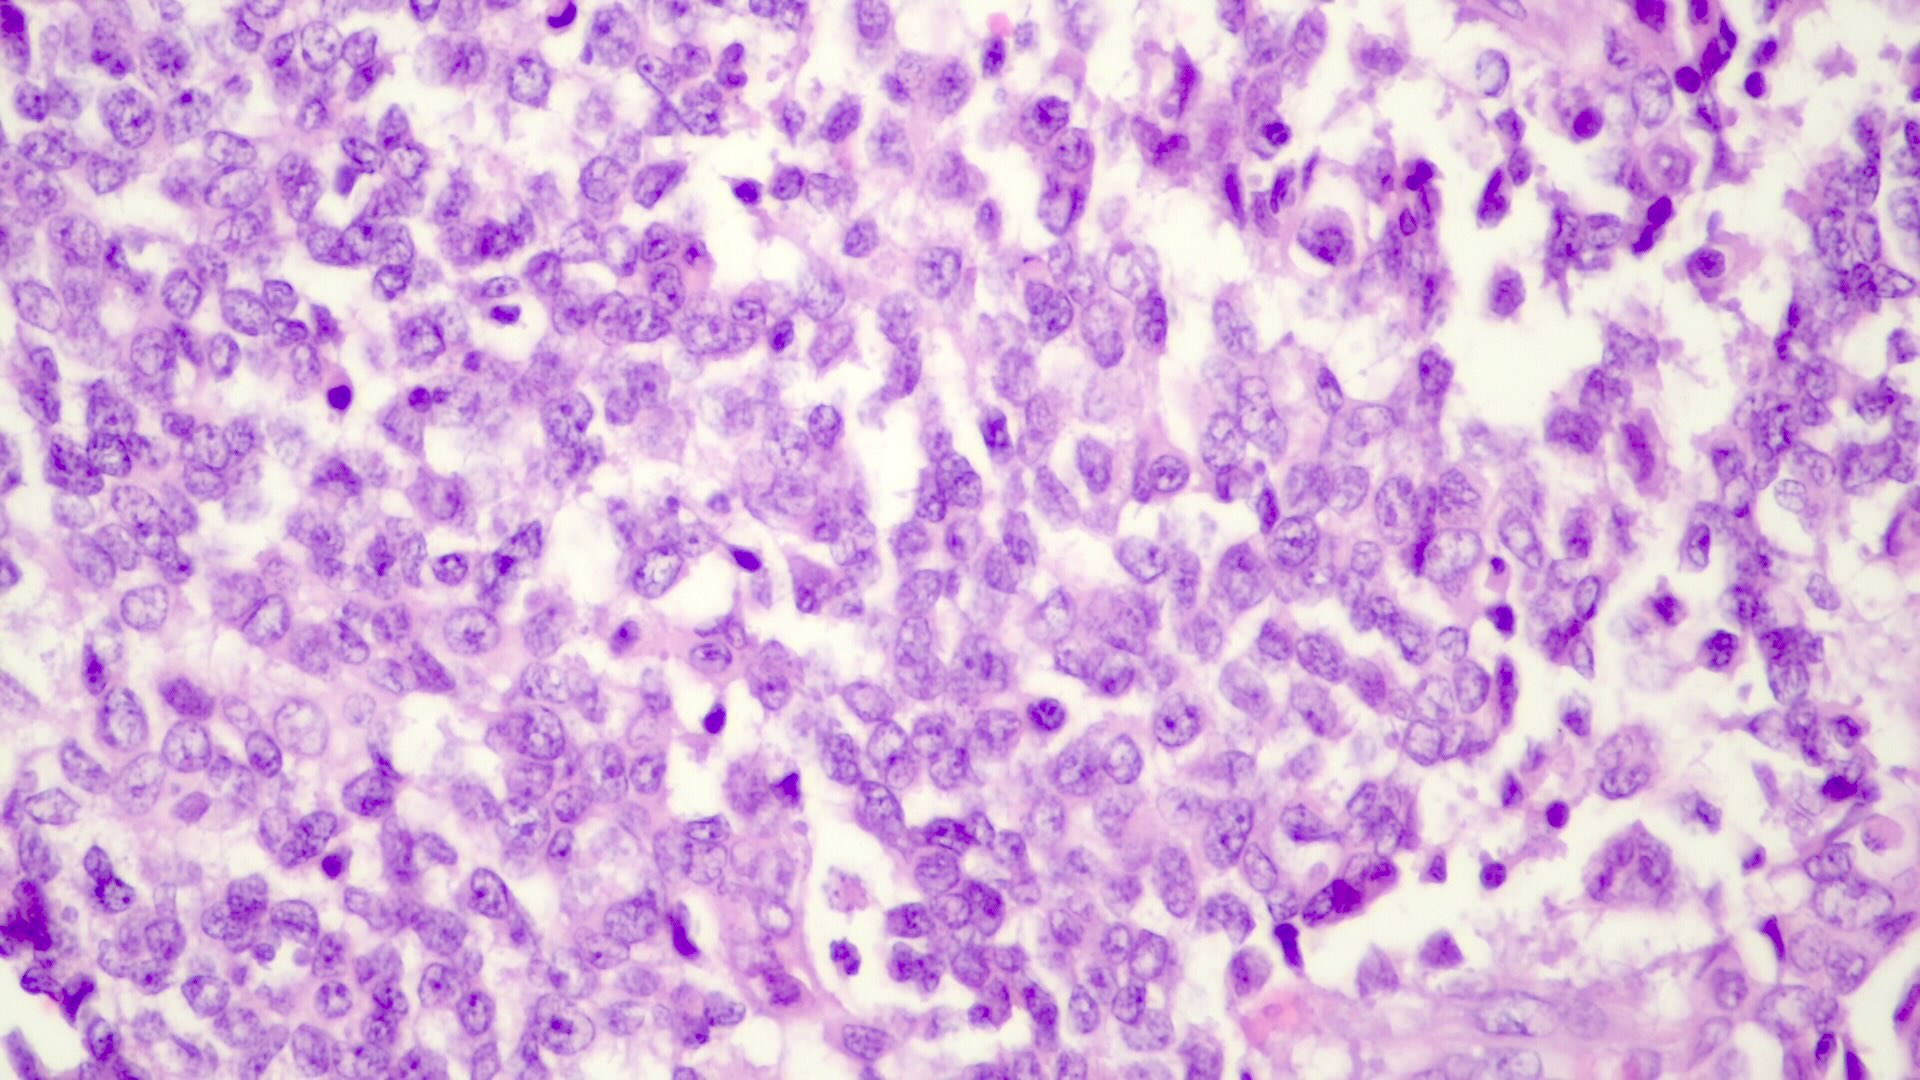

Embryonal pattern (19%)

- Sheets, ribbons, rosettes, papillary patterns or trabeculae of variable thickness with immature appearance, discohesive small cells with poorly defined cell borders, basophilic cytoplasm, high N:C ratio, prominent nucleoli, coarse chromatin and increased mitotic figures

- Extramedullary hematopoiesis, necrosis and vascular lakes are common; no fat, glycogen or bile

- Embryonal pattern (Pediatr Dev Pathol 2020;23:79)

- Resembles the developing liver at 6 - 8 weeks of gestation

- Solid nests or glandular / acinar morphology, with papillae and pseudorosettes

- Dark and granular cytoplasm without glycogen or lipids

- Enlarged nuclei with coarse chromatin, resembling blastemal cells

- Extramedullary hematopoiesis is usually absent

- Increased mitotic activity

Microscopic (histologic) images